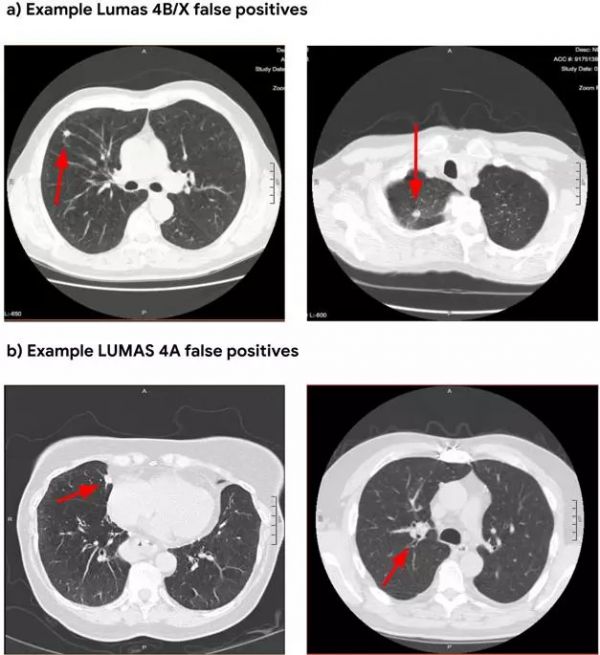

目前放射科医师在进行肺癌筛查时通常从单次CT扫描中查看数百张图像。在谷歌的案例中,其研究人员通过美国国立卫生研究院和西北大学的45000多次胸部CT扫描训练其机器学习算法,其中一些CT扫描结果显示出不同阶段的癌症特征。该算法通过从CT扫描生成3D模型来工作,生成全面的肺癌恶性肿瘤识别并预测专业医师肉眼很难看到的细微恶性组织或肺结节,有助于揭示可疑组织的生长速度。

为了测试该模型,谷歌要求其AI检查45,856个胸部CT扫描结果,并将该算法生成的报告与6位专业放射科医师检查的结果进行比对。谷歌表示,通过AI对肺癌患者检测的准确率提高了5%,误报率降低了11%以上。此外,这项研究在确定筛查高风险患者(如长期吸烟者)时,可将死亡风险降低约20%,大约50%的肺癌患者在接受治疗后依旧能够被诊断出来。